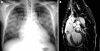

Acute dissection of the aorta can be one of the most dramatic cardiovascular emergencies. Classically, aortic dissection presents as sudden, severe chest, back, or abdominal pain that is characterised as ripping or tearing in nature. However, a timely diagnosis can be elusive in the event of an atypical presentation. In this report, the authors present two patients with painless aortic dissection who were misdiagnosed during their initial evaluation in the emergency department.